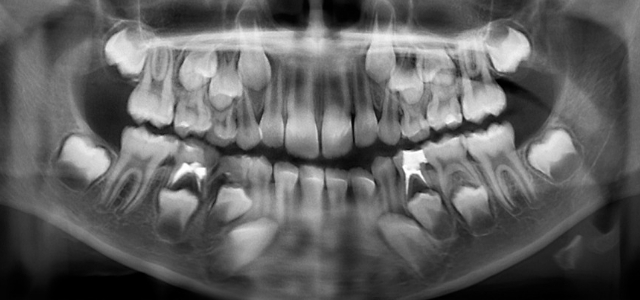

Un niño se quejaba de un fuerte dolor en la boca, por lo que decidió acudir al hospital Saveetha Dental College ubicado en Chennai, India. Al concluir la inspección se le realizó una radiografía y una tomografía, saliendo a la luz la existencia de más de 500 dientes en su boca.

El niño tenía una «estructura en forma de bolsa» en la boca, la tomografía reveló múltiples dientes rudimentarios. La situación del menor requirió cirugía, la cual duró más de 5 horas con un resultado favorable.

Al término del procedimiento quirúrgico el pequeño se quedó con 21 dientes, su caso será estudiado minuciosamente para saber las causas.